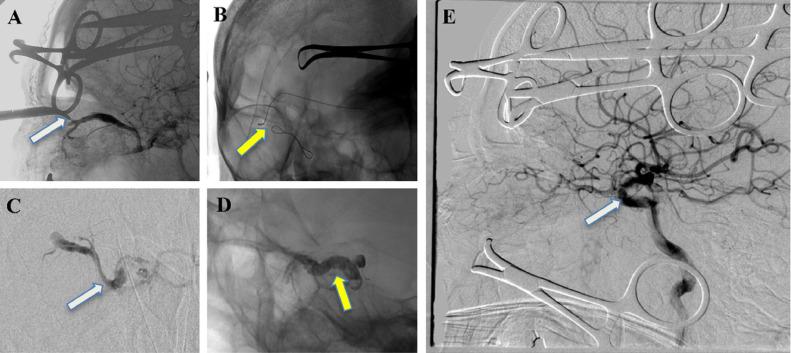

颈动脉海绵窦瘘(CCF)是一种血管畸形,其特征是一个或多个动脉流入源与海绵窦(CS)之间存在异常分流。它们可分为直接瘘和间接瘘。后者称为硬脑膜CCF,涉及颈内动脉或颈外动脉分支之间的硬脑膜瘘管连接。当传统路径不可行时,静脉的手术暴露是进入瘘管的唯一途径。我们介绍了一例通过混合方法成功治疗右侧硬脑膜CCF的患者病例。此外,通过文献综述,我们分析了这种方法可能带来的风险和益处。

https://cdn.ncbi.nlm.nih.gov/pmc/blobs/9917/9283805/29f2890724ae/gr2.jpg